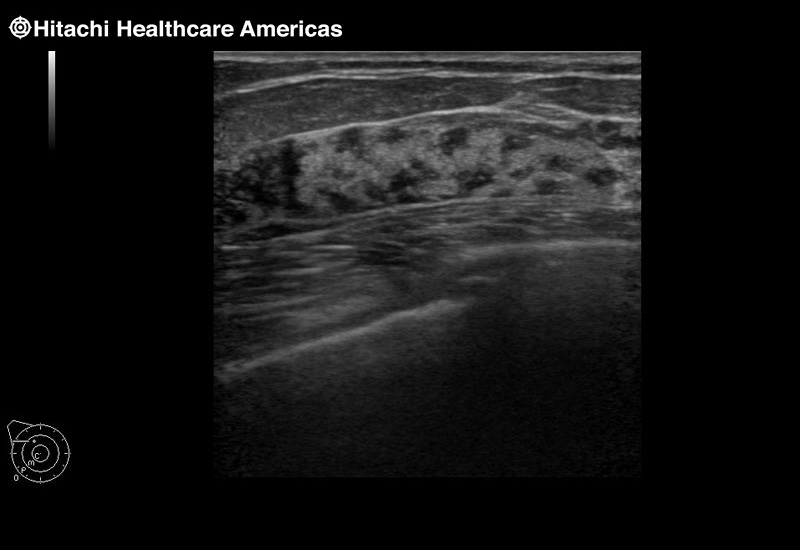

Superior guidance for all applications

Fujifilm Healthcare Americas is committed to designing tools that help surgeons navigate inside the human body and provide the necessary information to immediately make critical surgical decisions.

Fujifilm Healthcare's dedication to Surgeons provides outstanding ultrasound technology, professional support and the specialized tools necessary to best perform comprehensive real-time ultrasound imaging in Breast Surgery, General Surgery, Laparoscopic Surgery, Neurosurgery, Robotic Surgery and Surgical Oncology.

Recognized for our outstanding image quality, outstanding system reliability and intuitive use of cutting edge technology, Fujifilm Healthcare remains the standard in the field of Surgery.

Recognized for our outstanding image quality, outstanding system reliability and intuitive use of cutting edge technology, Fujifilm Healthcare remains the standard in the field of Surgery.